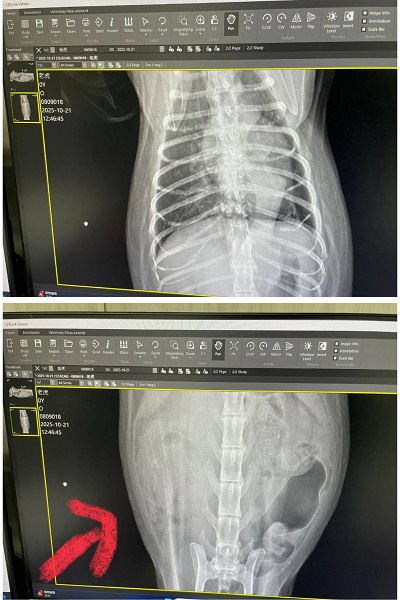

2025年6月2日回診的皮膚改善不夠理想、要更換黴菌藥,也還有些小顆粒要繼續刷洗,比較讓人擔心的是除了肝指數升高,紅血球及血容比持續下降,懷疑體內有其他地方在出血,因此在2025年6月16日回診的紅血球仍在下降及白血球也開始下降時,做超音波及X光檢查進一步查看,結果發現心臟尺寸較大,再加驗心臟快篩結果異常,且脾臟也有腫大、右腎上方有一個跟腎臟本身一樣大的腫瘤。

2025年10月因老虎瞳孔放大精神狀況不佳而於同月21日回診,目前體重下降有些快但目前食慾精神還算穩定,還沒有出現症狀,右腎腫瘤過大問題採安寧照護,暫時也不需要回診,有食慾不好的狀況,可再回診拿類固醇跟止痛等藥物舒緩。若狀況持續變差則可向醫院領取嗎啡貼片及止痛藥。

至目前老虎的精神食慾尚可,但已來到末期的安寧照護,只希望盡可能讓老虎在最後階段能減緩身體的不適。本筆醫助是2025年6月26日於專心醫院及2025年6月30日至2025年10月21日間於沐恩醫院的費用,包含血檢、超音波、X光及用藥。

老虎於6/16至沐恩回診,X光檢查發現心臟尺寸比較大,心臟快篩也是陽性,且超音波檢查發現右腎有跟腎臟差不多大的腫瘤,腫瘤實際狀況需要CT才能確認,沐恩林院長建議先至心臟專科檢查心臟以確認是否可以進行CT跟手術,但協會顧慮,老虎的年紀及目前狀況可能無法承受手術,但就算最終決定不手術,也可以看醫生建議是否需要服用心臟藥物。

2025/10/21 老虎 沐恩 林院長

體重:4.435kg (6/30是5.61kg)

一、看診情形

請醫師協助剪指甲。體重掉稍微比較多,腫瘤引起比較有關係

皮膚跟體力有影響關係,右腎腫瘤過大只做安寧照護就先維持

胸有點不明物體不確定是什麼物體(也有可能是瘦太快皮膚皺摺陰影),有明顯的呼吸聲,也不像肺部轉移物質,超音波檢查是沒事。